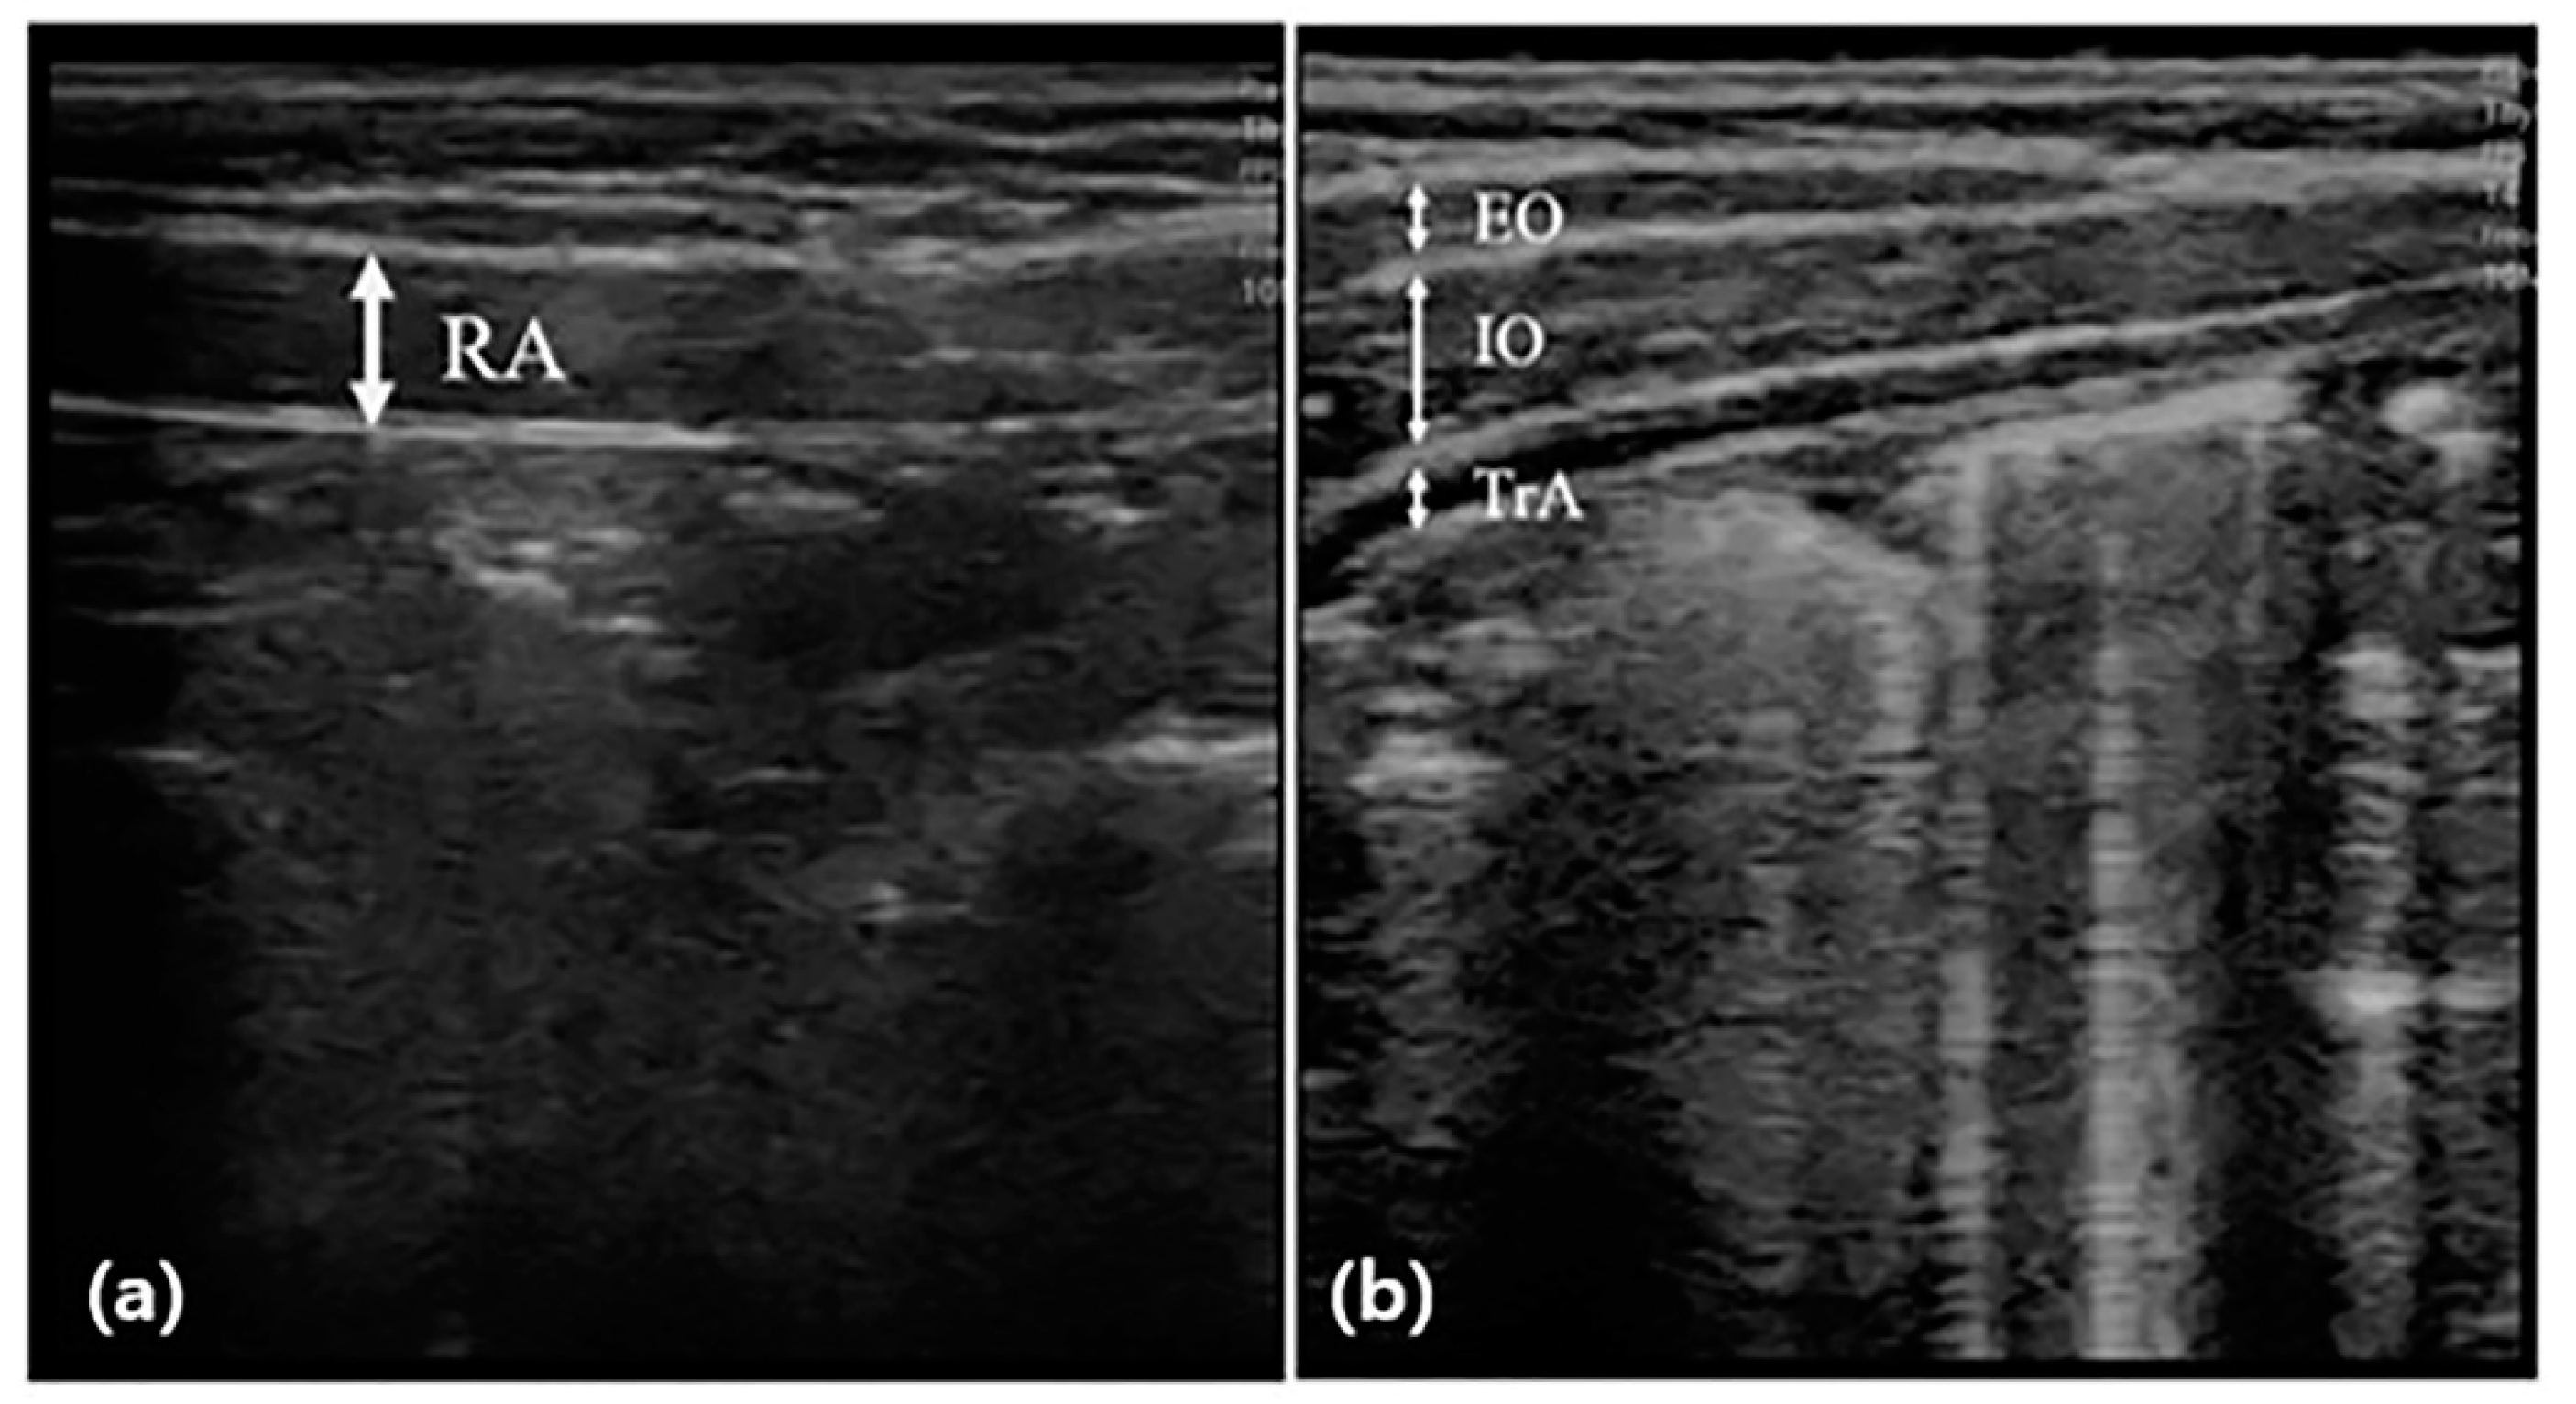

2.2.1. Abdominal Muscle Thickness